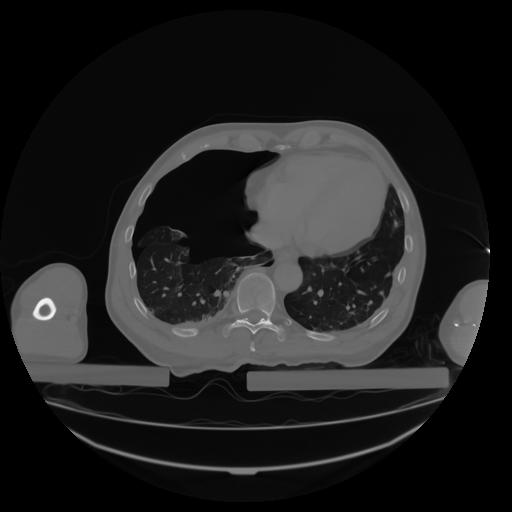

27 CUERPO,CE,Axial,3.0,CUERPO,,